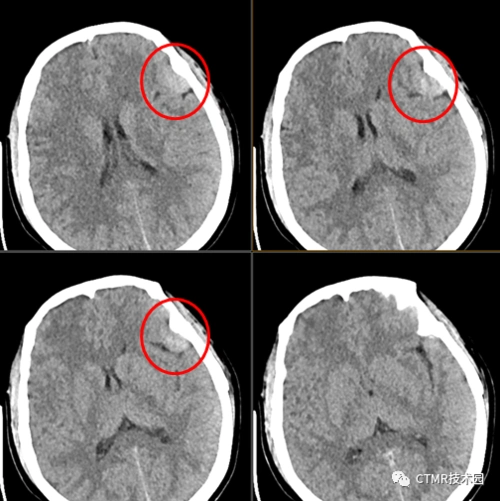

外院检查:报告大脑镰脂肪瘤来我院检查:本院ct:大脑镰钙化经验总结

易误诊为出血的大脑镰钙化,你会看吗?

红箭所指的大脑镰局部呈连续的长条状高密度影,容易被误诊为少量蛛血